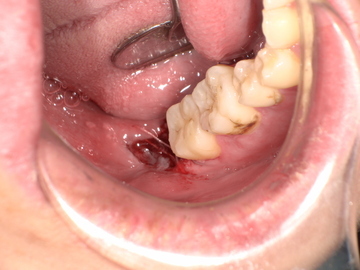

Before(下親知らずの抜歯前) 虫歯のある状態で埋まっている親知らず 抜歯前の骨の状態のレントゲン像

拝見したところ、一部分のみ生えている右下の親知らず(第3大臼歯/8番)と右下の奥歯(第2大臼歯/7番)との間で、歯肉の腫れが認められました。

次に局所麻酔を行い、親知らず周囲の歯肉を切開して骨を露出させます。骨の中で横に生えた状態で埋まっている親知らずはそのままでは抜くことができないため、親知らず周囲の骨を一部分削り取り、抜きやすいようにします。

親知らずを複数に分割してから、全て取り除きました。抜歯後は切った歯肉を元の位置に戻し、糸で縫って傷口を閉じます。